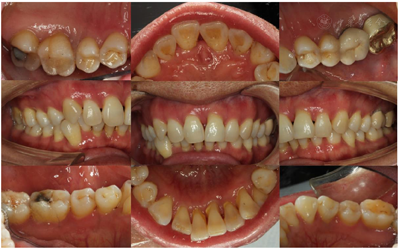

12年后复查时,口腔卫生状况良好,牙龈色偏粉,全口探诊4~6 mm,后牙区个别位点7~9 mm,探诊出血阳性率(89.3%比55.3%)和PD≥5 mm(38.6%比24.4%)百分比均下降,全景片显示牙槽嵴顶骨白线清晰、连续。

本病例中患者在经过1轮完善的牙周基础治疗后症状明显改善,自此于外院门诊行长达7年的洁治术。与7年前相比,可见牙槽骨有明显的降低。之后每年定期进行牙周维护治疗,可见牙槽骨硬骨板出现,连续。

该病例历经12年的牙周随访治疗,影像学显示牙槽骨维持稳定,患者16、26、36、46仍可探及深牙周袋,与患者反复沟通后,考虑行引导组织再生术以期获得牙周组织再生。